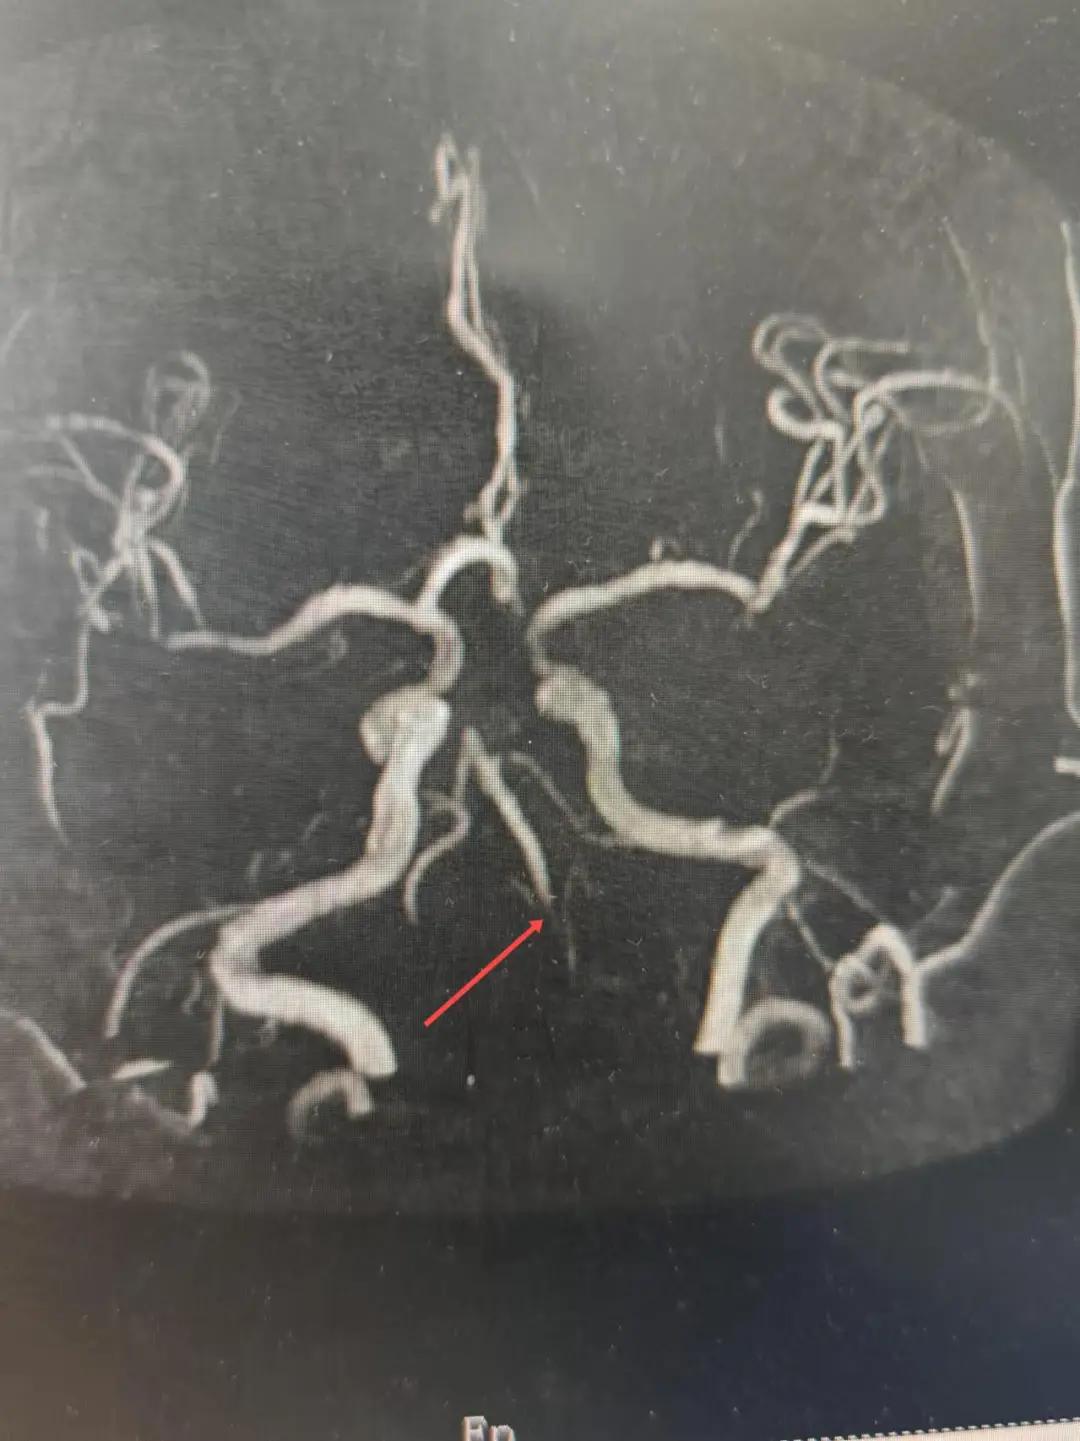

2024年12月19日,漯河市中醫(yī)院腦一科收治了一位79歲的女性患者。患者在入院前2小時(shí)出現(xiàn)言語不利,右側(cè)肢體無力。腦一科醫(yī)師關(guān)卓杰接診后,全面評估患者病情,給予其靜脈溶栓,并急查頭顱MR。影像可見腦干、雙側(cè)枕葉、左側(cè)海馬旁回及丘腦新發(fā)梗塞灶,基底動脈閉塞。患者在靜脈溶栓完畢后仍出現(xiàn)陣發(fā)性言語不利、右側(cè)肢體無力、頭暈。立即進(jìn)行科室間會診,副主任醫(yī)師彭壯考慮患者出現(xiàn)上述癥狀與其基底動脈閉塞后顱內(nèi)動脈代償不良有較大關(guān)系,且基底動脈閉塞有較高的致死率與致殘率,建議行急診取栓,降低患者死亡及殘障風(fēng)險(xiǎn)。家屬了解病情,知情同意后要求行介入治療。

磁共振MRA提示基底動脈閉塞